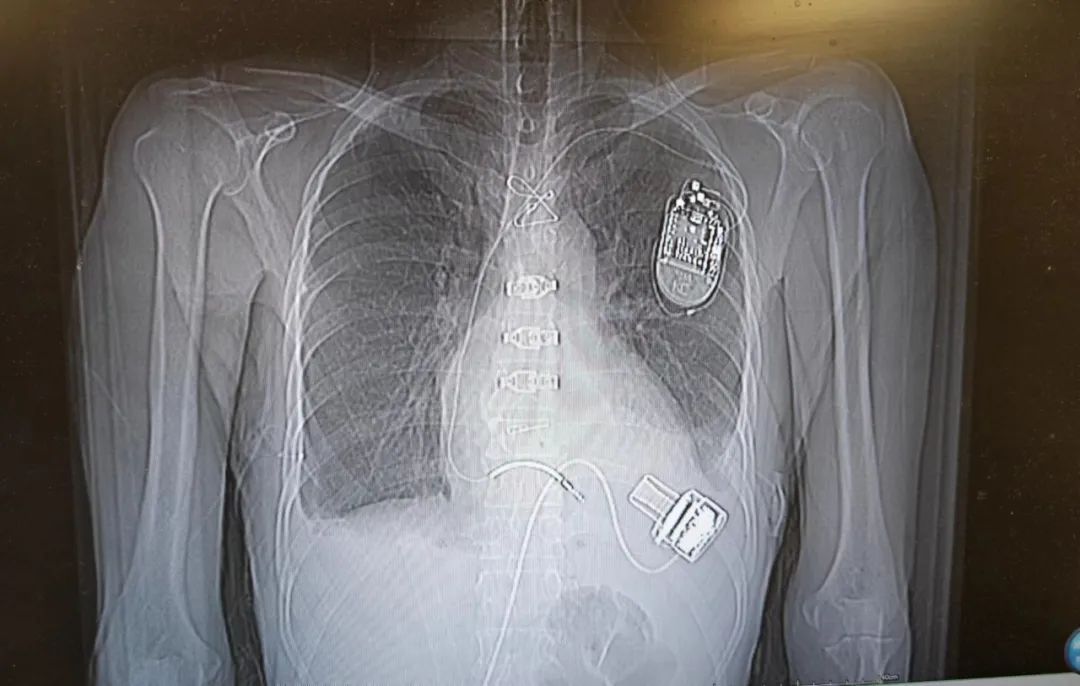

置入心室辅助装置后胸片

利军安装的是左心室辅助装置。这场不简单的手术,由赵强副院长带领的心室辅助团队负责。这个由心外科、超声科、麻醉科、监护室、体外循环等多个科室和领域的专家组成的团队,大家集思广益,在充分评估患者右心室功能基础上,制定了详细的手术方案,以及术中术后完善的右心室功能保护和调整方案。